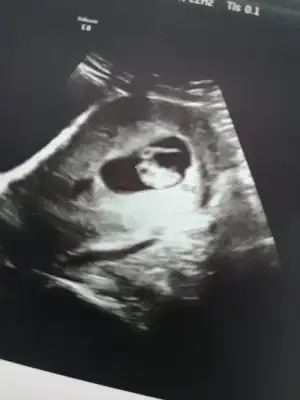

Merhaba 7 buçuk haftalık tahmin ederseniz sevinirim☺️

21,7 KB · Görüntüleme: 67

18,8 KB · Görüntüleme: 74